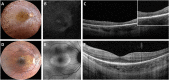

Methods: An Italian cohort of 48 male patients (from 31 unrelated families) with RPGR-associated RP was clinically assessed at a single center (mean follow-up = 6.5 years), including measurements of best-corrected visual acuity (BCVA), Goldmann visual field (GVF), optical coherence tomography (OCT), fundus autofluorescence (FAF), microperimetry, and full-field electroretinography (ERG).

Results: Patients (29.6 ± 15.2 years) showed a mean BCVA of 0.6 ± 0.7 logMAR, mostly with myopic refraction (79.2%). Thirty patients (62.5%) presented a typical RP fundus, while the remaining sine pigmento RP. Over the follow-up, BCVA significantly declined at a mean rate of 0.025 logMAR/year. Typical RP and high myopia were associated with a significantly faster decline of BCVA. Blindness was driven primarily by GVF loss. ERG responses with a rod-cone pattern of dysfunction were detectable in patients (50%) that were significantly younger and more frequently presented sine pigmento RP. Thirteen patients (27.1%) had macular abnormalities without cystoid macular edema. Patients (50%) with a perimacular hyper-FAF ring were significantly younger, had a higher BCVA and a better-preserved ellipsoid zone band than those with markedly decreased FAF. Patients harboring pathogenic variants in exons 1 to 14 showed a milder phenotype compared to those with ORF15 mutations.